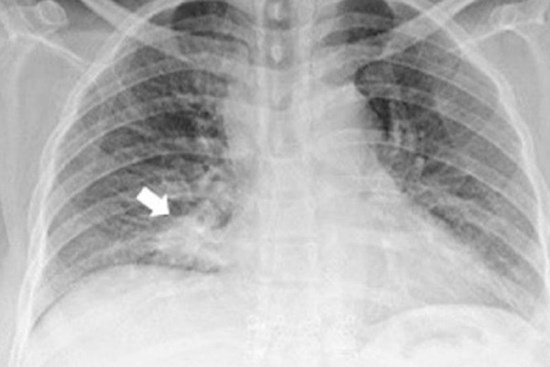

Cách nhận biết dấu hiệu khi ho cảnh báo nguyên nhân do ung thư phổi

Cách bạn ho có thể xác định nguyên nhân do ung thư hay liên quan bệnh đường hô hấp.